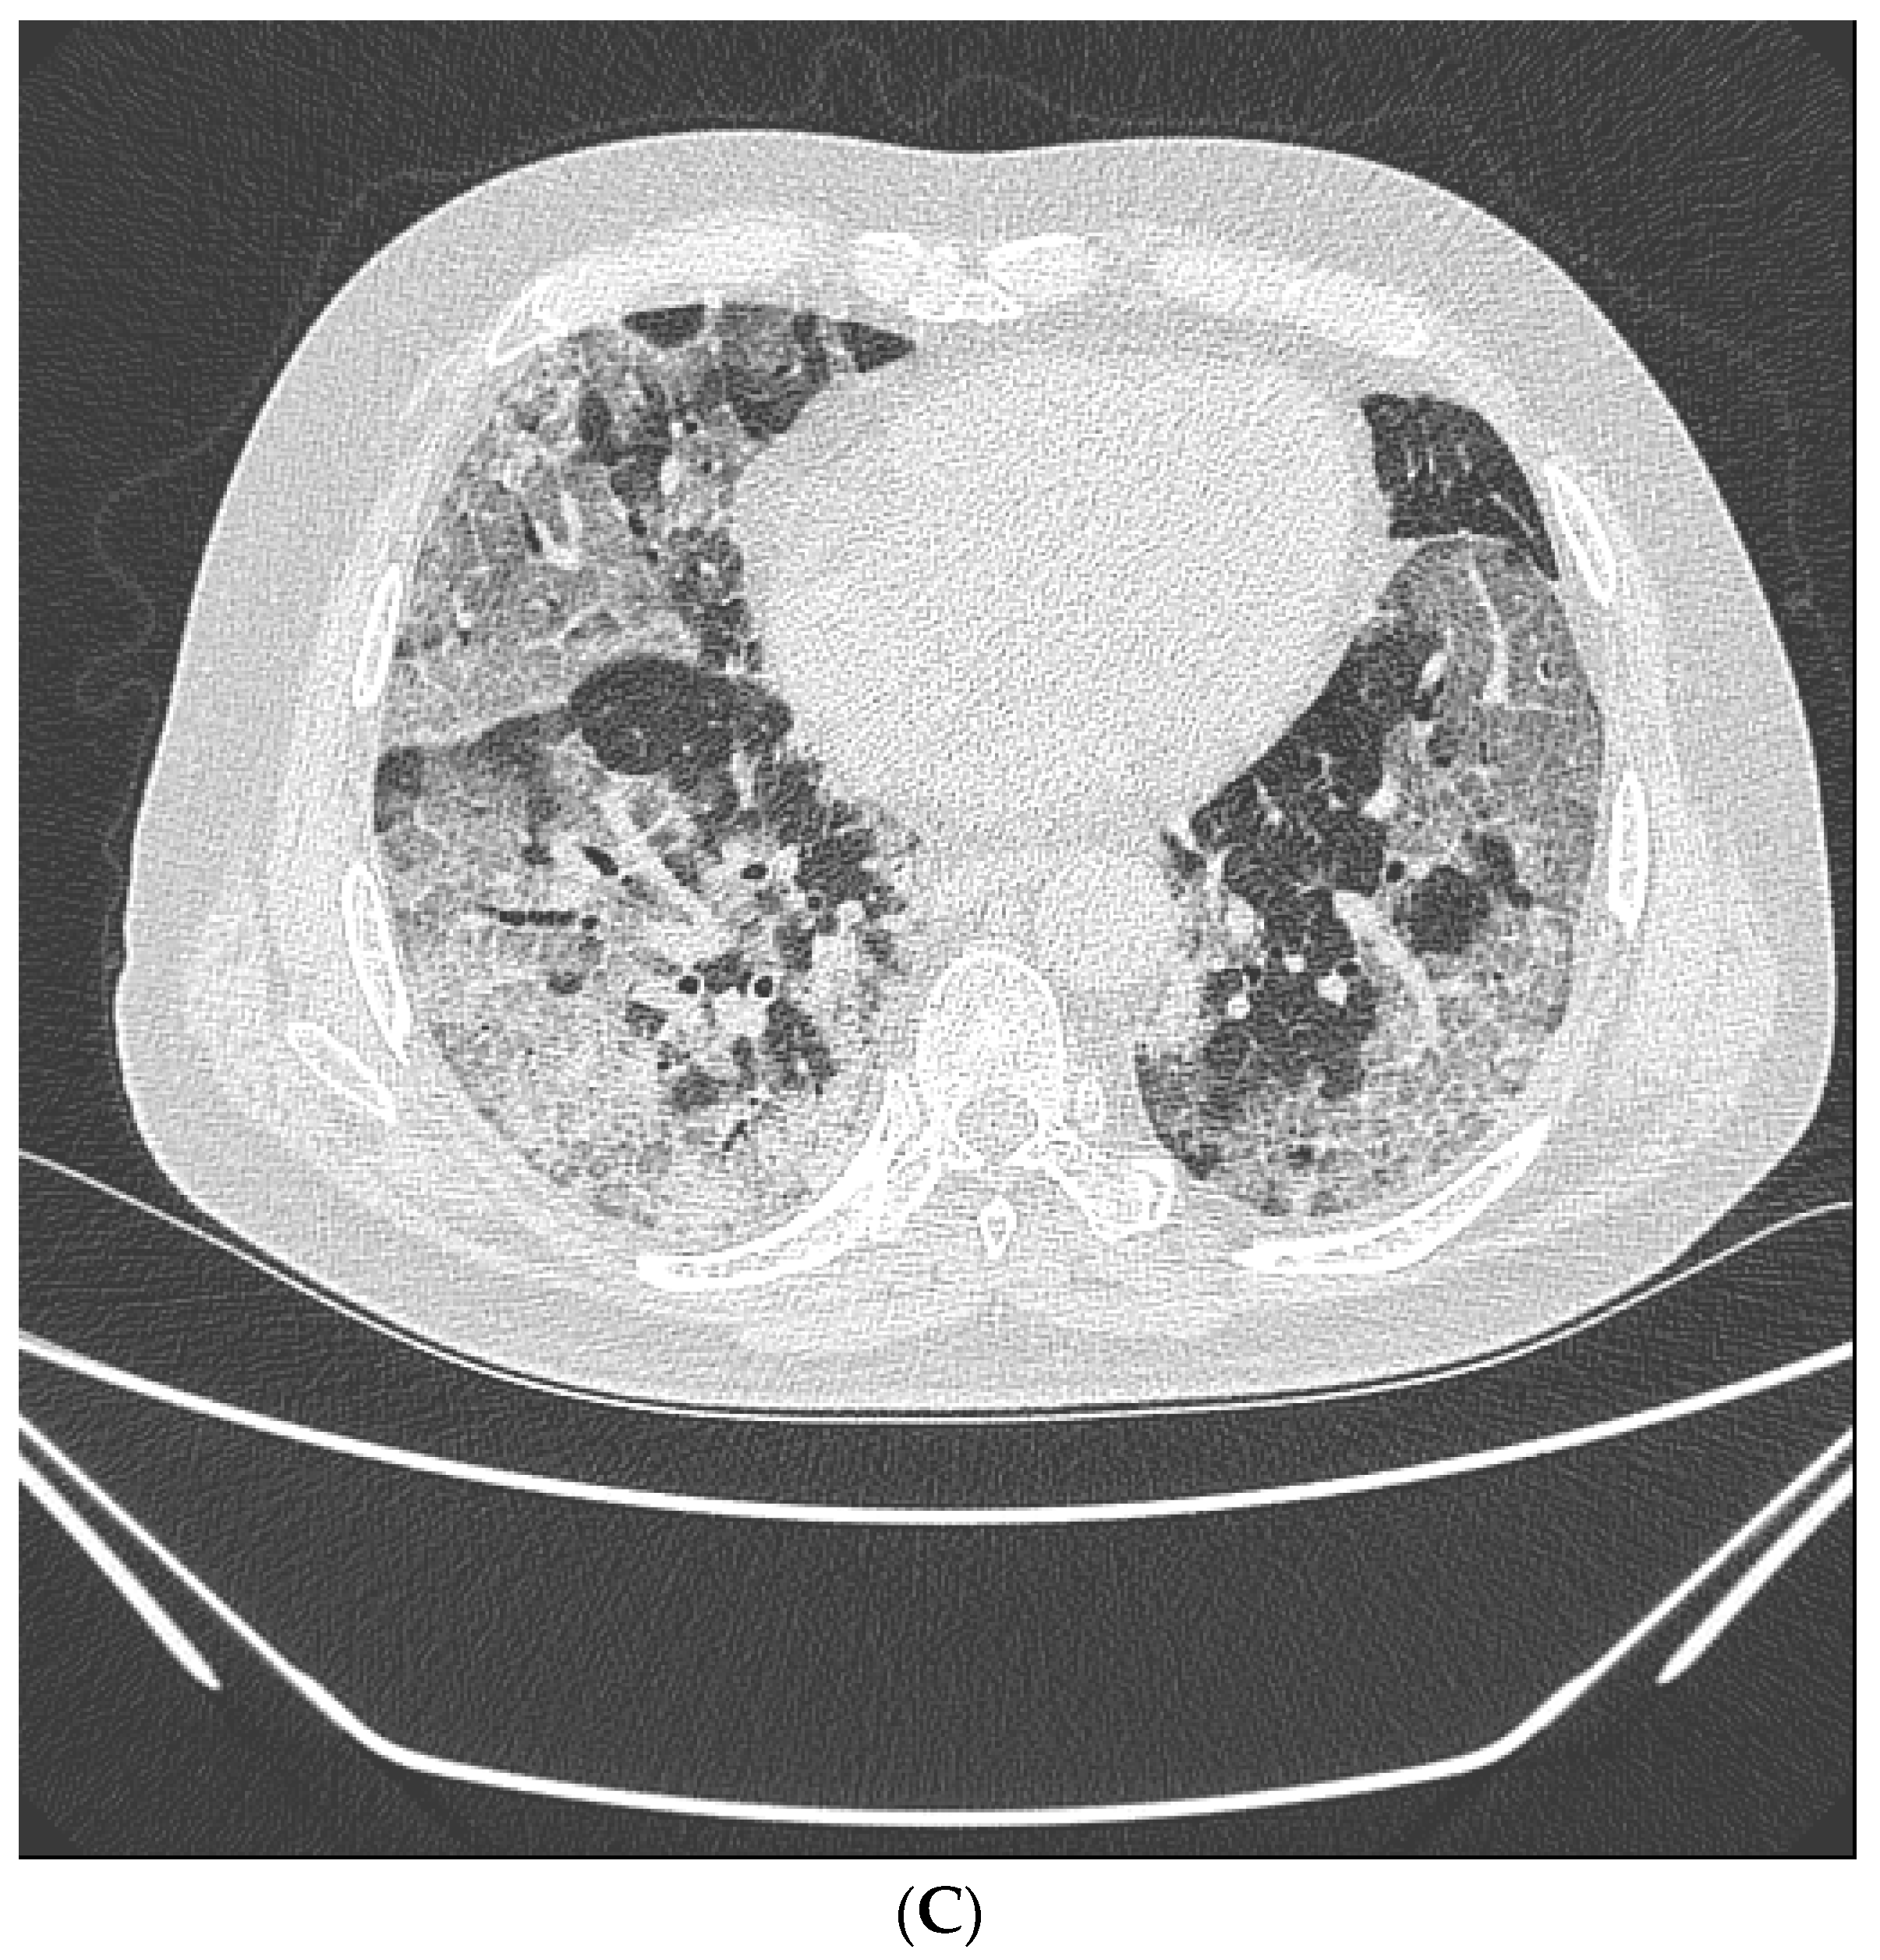

LDCT were obtained on symptomatic patients at high risk of screening with a 64-section scanner (Brilliance CT, Philips Healthcare) [16]. One radiologist (over 15 years of experience) and one pulmonology specialist (over 8 years of experience) retrospectively reviewed all LDCT images. Lobar distribution was assessed by observing the number of involved lobes, laterality, cephalocaudal distribution, and axial distribution [17]. In terms of pattern, ground glass opacity (GGO), consolidation, and crazy-paving pattern was assessed according to the definitions based on the Fleischner Society Nomenclature Committee recommendations [17,18]. (Figure 2A–C) Observation of the following characteristics was considered a typical finding for COVID-19; (1) peripheral, bilateral, GGO with or without consolidation or visible intralobular lines (“crazy-paving”), (2) Multifocal GGO of rounded morphology with or without consolidation or visible intralobular lines (“crazy-paving”), (3) Reverse halo sign or other findings of organizing pneumonia [18].

Figure 2.

Typical findings for COVID-19 on CT scans. (A) Ground-glass opacity shows as a modest increase in lung attenuation on lung window CT images, not obscuring the pulmonary vessels. (B) Consolidation appears as high-density patchy opacities that obscure the margins of vessels and airway walls, inside which air bronchogram (arrow) could be observed. (C) Crazy-paving pattern appears as thickened interlobular septa and intralobular lines superimposed on a background of ground-glass opacity.